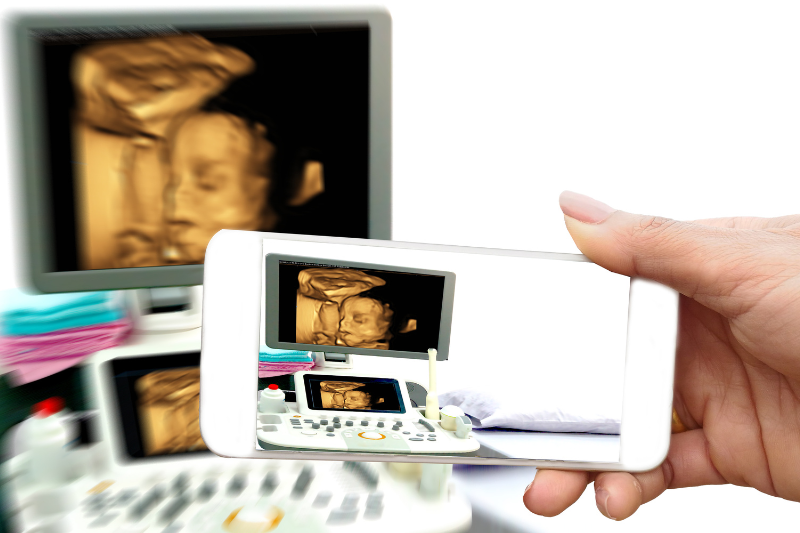

Poznato je da 3D i 4D ultrazvučni pregledi omogućavaju da se sagledaju razni detalji bebinog tela na jedan savremen i dinamičan način u odnosu na standardni 2D ultrazvuk. Međutim, ova vrsta pregleda se vrši ukoliko ginekolog porceni da postoji potreba za njim, iz razloga što su ovakvi pregledi indikovani u slučaju kada je potrebno sa više detalja sagledati bebino telo kako bismo dobili veći broj informacija u vezi njenog zdravlja. Ultrazvučni 3D i 4D pregledi omogućavaju da se sagledaju neke anomalije tela bebe kao što je na primer rascep usne ili kičmenog stuba, zatim od koristi su u proceni gutanja, mimike lica i pravca ruku i nogu. Drugim rečima, oni nisu deo standardnih pregleda u trudnoći.